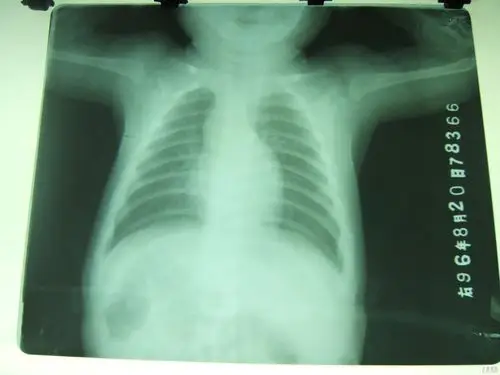

正常小孩正位胸片dscf3467.jpg